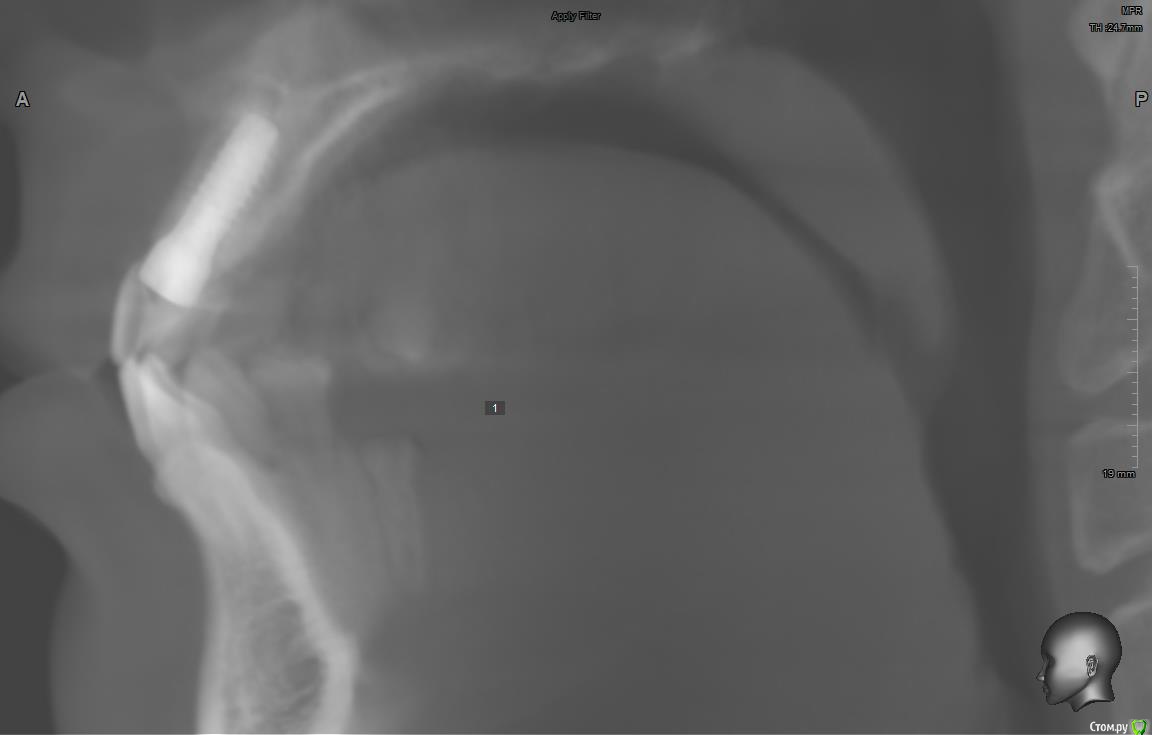

jm3300 Опубликовано 11 сентября, 2019 Поделиться Опубликовано 11 сентября, 2019 Имплант( система, производитель) не известен, формирователи подобные не видел, шестигранные отвертки не подходят( на формике отверстие под четырехгранник). Данных на имплант у пациента нет. В клинике, где ставили, якобы, не помнят что ставили. Может кто встречался с ними? Ссылка на комментарий

АнтонТЛТ Опубликовано 11 сентября, 2019 Поделиться Опубликовано 11 сентября, 2019 (изменено) Что за мода выкладывать срезы Кт, на которых всё фонит. Лучше уж прицельный снимок. Возможно это конмет, у них квадратный шлиц. Изменено 11 сентября, 2019 пользователем АнтонТЛТ 2 Ссылка на комментарий

dr Alexandr Опубликовано 14 сентября, 2019 Поделиться Опубликовано 14 сентября, 2019 Похож на Конмет, у этой системы своя протетика и ортопедический набор! Отвёртка у них 6 гр только меньше, нужно попробовать выкрутить фдм, там понятнее будет 1 Ссылка на комментарий